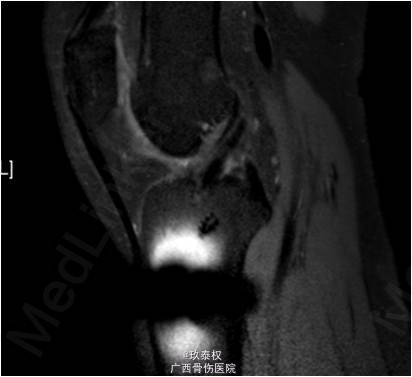

查体:双下肢无畸形,左膝关节无静脉曲张、肿胀等,皮温正常,关节间隙压痛,麦氏征(-),蹲走试验(-),过伸试验(-),过屈试验(-),浮髌征(-),髌骨加压研磨试验(-),前抽屉试验(-),后抽屉试验(-),侧方应力试验(-),lachman征(-),关节活动度0-135度,股四头肌无明显萎缩,肌力正常;肢端血运、感觉、活动正常。右下肢及双上肢其余关节未见明显异常。 辅助检查:X线平片及MRI检查未见明显异常。

诊断:1.左膝关节前交叉韧带重建术后;2.左膝关节半月板修补术后。行左膝关节镜检及门型钉拆除术。术后开始行股四头肌肌力训练及踝泵训练,术后第2天开始主动关节屈伸训练,屈膝达90°,术后第3天可完全负重。

现患者随访1个月,左膝关节前抽屉试验(-),lachman征(-),已全面恢复日常活动。 前交叉韧带重建后的交叉韧带胫骨和股骨端固定,目前股骨端常采用Endobutton、生物横杆或生物挤压钉进行固定,而胫骨端常采用生物挤压钉和门型钉进行固定。术后半年后患者腱骨愈合良好的情况下可行门型钉拆除术。